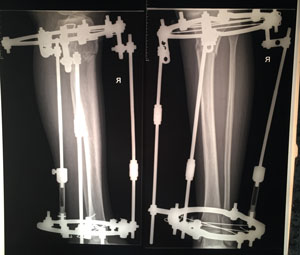

Дата операции - 07.05.2019г.

Дата снятия аппаратов - 20.08.2019г.

Срок сращения - 102 дня.